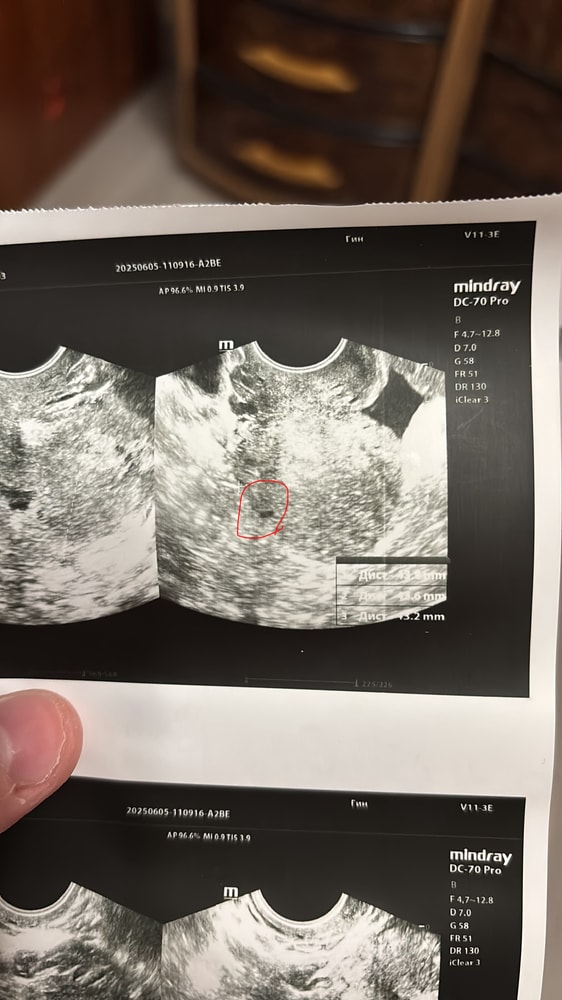

Месячные пришли на 8 дней раньше , очень скудные , продолжаются уже 6 день. Болей нет, тест отрицательный, была на узи малого таза трансвагинально, со слов врача все в порядке. Напрягает темное пятно на снимке